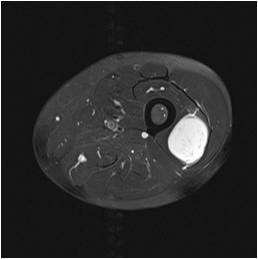

Gallery of Unlabled Radiographs from Lecture (Dr. French) - 2020

Click a thumbnail to enter the gallery display. Click the file name link at the bottom left of the gallery display to view the image at high resolution.

Labeled Plates from Lecture (Dr. French) - 2020

RadiologyLowerLimbThoraxQuestionPoolLabeled_01_2020.pdf

Click right side of plate to step forward or left side of plate to step backward.